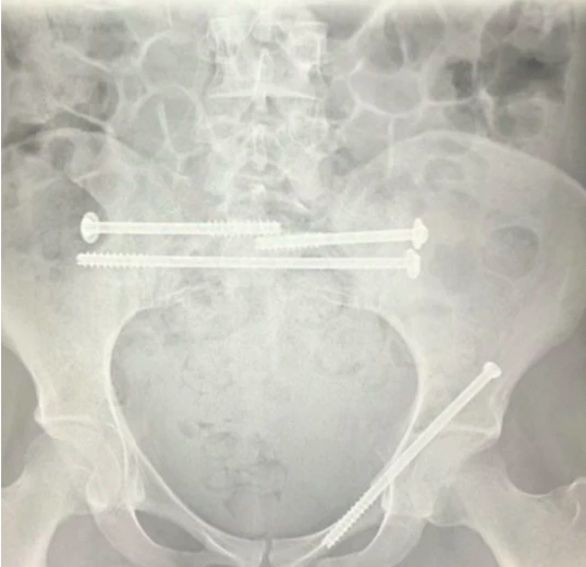

في المستشفى، كان الأطباء قلقين من أنها لن تمشي مرة أخرى بسبب شدة إصاباتها، حيث كُسر ظهرها وحوضها وساقاها وتحطم كاحلها في 30 مكاناً. ولكن لحسن الحظ، بعد 12 أسبوعاً فقط من الحادث، بدأت صوفي خطواتها الأولى في منزلها.